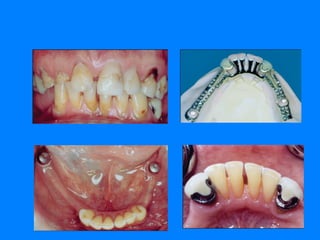

SE DEBE CONOCER LAS CARACTERISTICAS CLINICAS DE LOS DIEFERENTES TEJIDOS DE SOPORTE

HABLAR DE SOPORTE PARA UNA RESTAURACION PARCIAL REMOVIBLE DETERMINA  DOS TIPOS DIFERENTES DE TEJIDO   SOPORTE DENTAL: BRINDADOS POR LOS DIENTES PILARES A EXPENSAS DE SUPERFICIES HORIZONTALES QUE CONTROLEN FUERZAS DE DIRECCION VERTICAL. SOPORTE MUCOSO: BRINDADO POR LA CRESTA DEL REBORDE RESIDUAL Y EL PALADAR. LA RESILENCIA DEL TEJIDO MUCOSO PERMITE LA GENERACION DE MOVIMIENTO PARA LA BASE PROTESICA QUE SE SOPORTA SOBRE ELLA .

Restauración dento-muco soportada:   presencia de un mayor número de dientes naturales los cuales pueden ser dientes pilares, reduce la extensión de los rebordes residuales   Restauración muco-dento soportada:   presencia de un menor numero de dientes naturales teniendo mayor participación el tejido mucoso